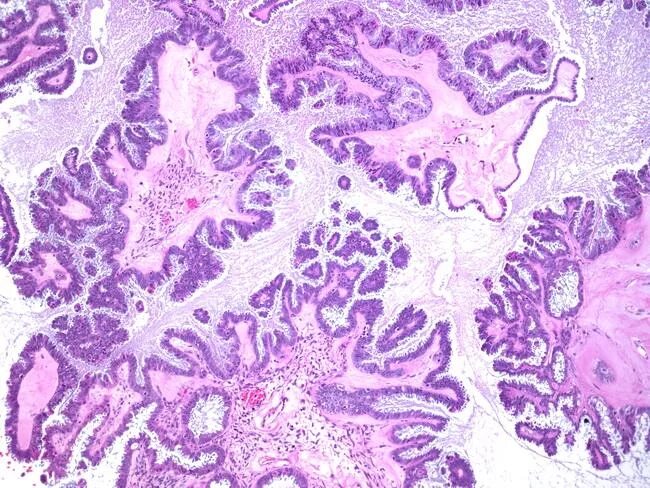

Гистология цистаденомы